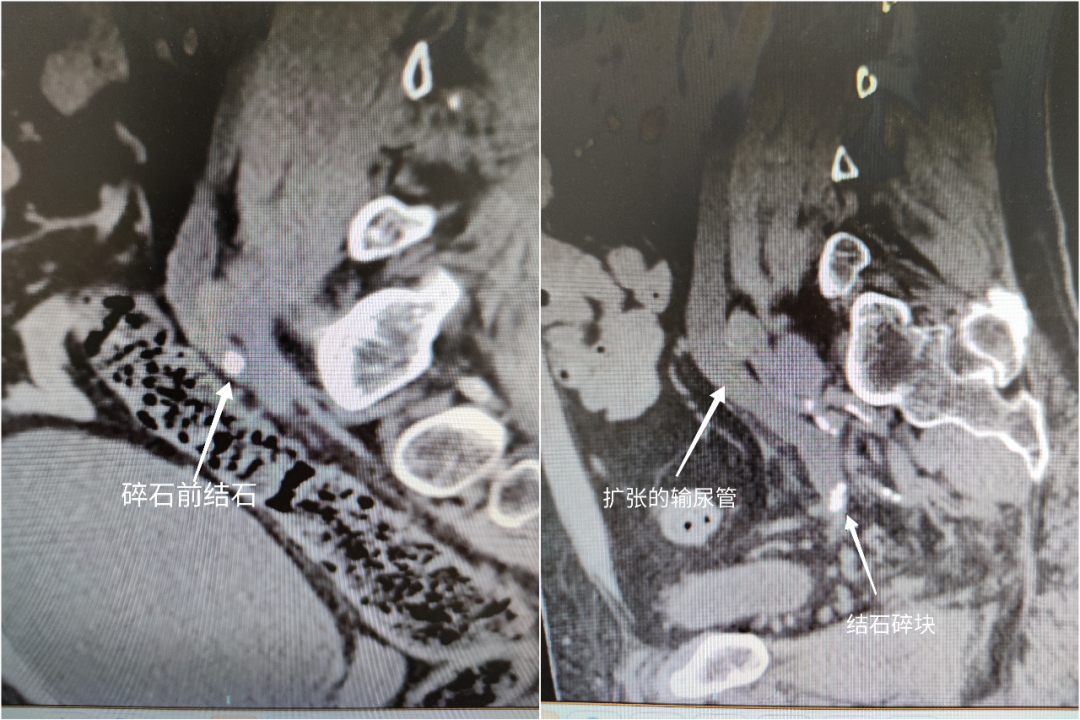

在家人的陪伴下,王先生來到太原市中心醫院急診做進一步檢查,行泌尿系CT檢查提示左側輸尿管中下段多發結石,血常規提示白細胞23.5X10^9/L,中性粒細胞95.4%,血壓90/60mmHg,心率115次/分。

入院后,泌尿科汾東病區專家考慮王先生輸尿管下段梗阻是導致感染性休克的主要原因。隨即,給予王先生抗感染、糾正休克治療。三天后,王先生的病情有所好轉,經研究討論,科室專家為王先生制定了安全周密的手術方案。

其中,體外沖擊波碎石由于成本低、時間短、費用少,更容易被患者接受。但其也有相當多弊端,不是所有的尿路結石都適合體外沖擊波碎石,比如肥胖人群、輸尿管中下段結石(腸道氣體及骨盆干擾)、堅硬結石等都不適合體外碎石。碎石不確切、排石不徹底,更有甚者形成輸尿管“石街”導致輸尿管梗阻及感染性休克危及生命。